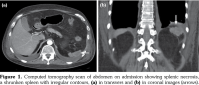

In clinical admission, his physical examination showed no evidence of systemic infection with a body temperature of 37.2°C. Laboratory findings at his first admission were summarized in Table 1. Computed tomography (CT) scan revealed a cavitary lesion of 6 mm in diameter located in the left upper lobe (which was also seen in his previous chest CT) besides a shrunken spleen as a recent finding (Figure 1).